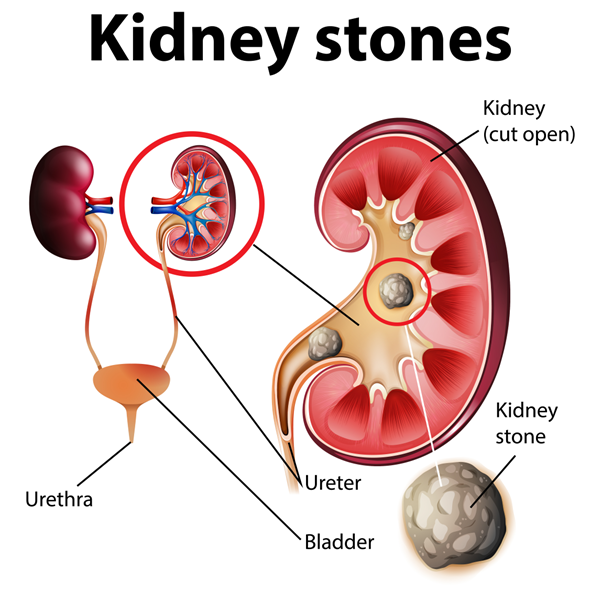

Kidney Stones: A Painful Reminder from Within

Introduction: Kidney stones, those tiny but mighty mineral deposits formed within our kidneys, have been causing havoc in the human

Coping with Kidney Stones: Causes, Symptoms, and Treatment

Kidney stones can be a painful and uncomfortable experience for anyone who suffers from them. Kidney stones are small, hard